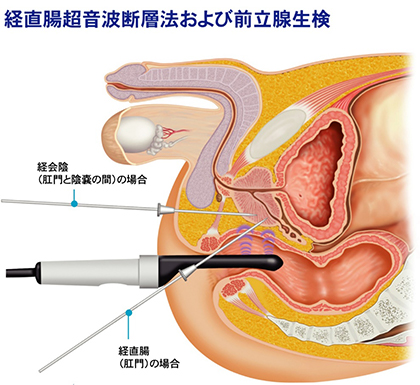

尿道狭窄症とは 堀口明男 Official Site

尿道狭窄症とは 堀口明男 Official Site

尿道形成術とは 堀口明男 Official Site

前立腺針生検 経会陰式 のイラスト 医療のイラスト 写真 動画 素材販売サイトのメディック Medick

前立腺針生検 経会陰式 のイラスト 医療のイラスト 写真 動画 素材販売サイトのメディック Medick